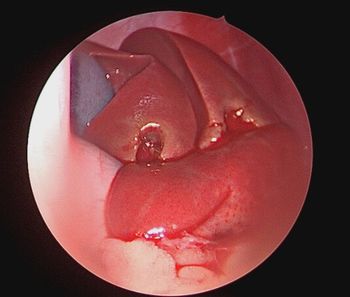

Skittles, a 6-month-old calico, presented at Texas A&M’s Small Animal Teaching Hospital with her jaw locked shut on one side and fractured on the other.